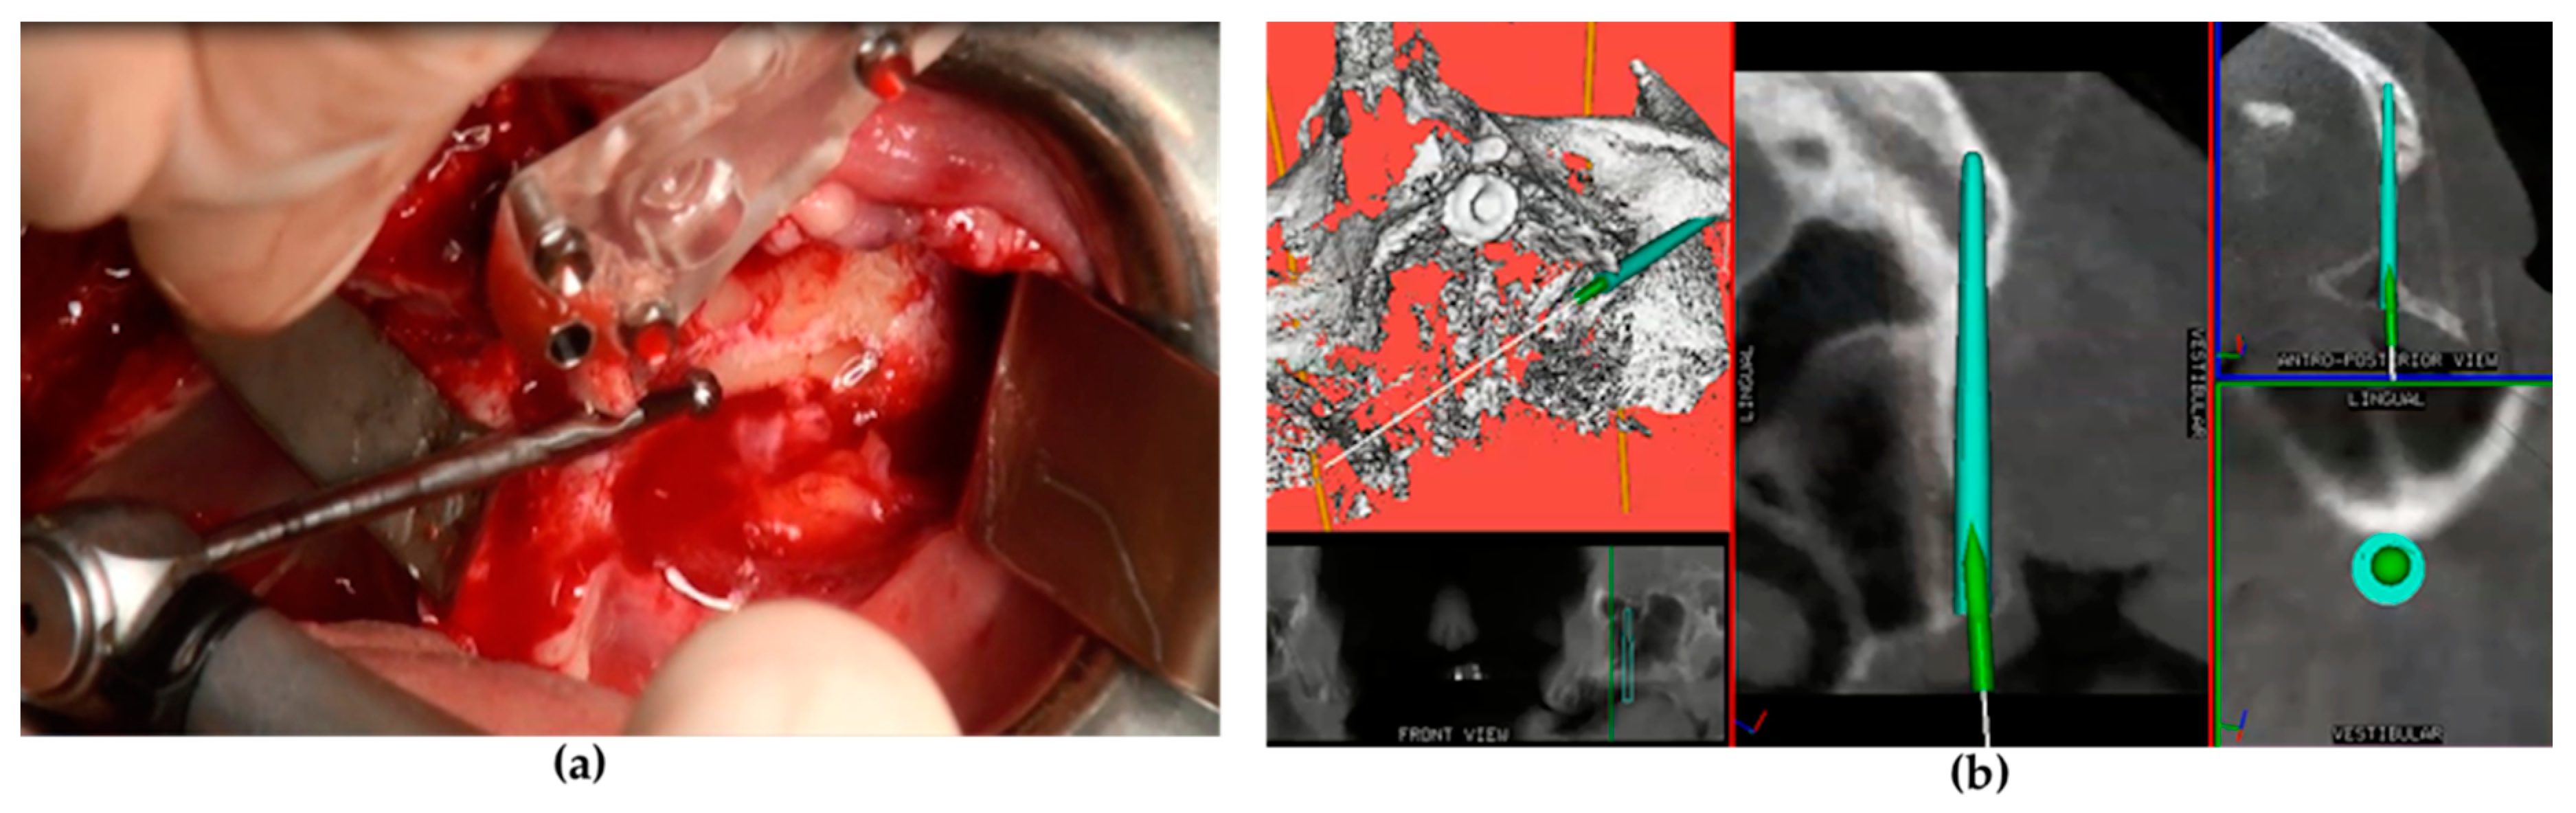

Following general anesthesia and local infiltration of articaine with adrenaline (1:100.000), a mid-crestal incision was made at the level of the alveolar ridge keratinized mucosa with two oblique distal incisions at the level of the maxillary tuberosity. A mucoperiosteal flap was raised to expose the alveolar crest, lateral maxillary wall, pyriform aperture, infraorbital foramen, lateral orbital border, and zygomatic bone. A series of drills mounted on a straight or an angled handpiece (Figure 1a) and an implant motor (Surgysonic® Moto, Esacrom, Imola, Italy) were used to penetrate the alveolar process and the zygomatic bone according to the proposed implant diameter. In some cases, the initial steps were performed using an ultrasonic instrument. The zygomatic implant trajectory was verified in real time by using the ImplaNav dynamic navigation system (Figure 1b) with an intraoral reference tool.

A maxillofacial type navigation system involving the use of an extraoral reference tool (onto the cranial bone) was employed in three oncologic patients in whom the residual maxillary bone was not sufficient for the fixing of the intraoral reference tool. After a final evaluation carried out by a depth gauge, zygomatic implants (Southern Implants, Irene, South Africa) were positioned via the use of implant motor or manually using a fixture mount. Standard zygomatic implants were placed in patients from the atrophic group and in oncologic patients when the implant collar was surrounded by the residual crestal bone (Figure 2a). The oncologic type of zygomatic implant was placed when there was only soft tissue around the implant collar (Figure 2b).

Figure 2. The zygomatic implant was placed and the conical abutment was screwed before suturing. (a) The standard type of zygomatic implant was used for patients with maxillary atrophy. (b) An oncologic type of zygomatic implant with a machined coronal part was used for implant sites that lacked crestal bone.